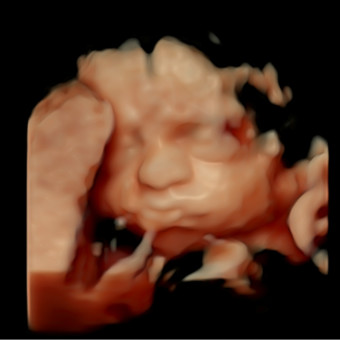

Elaine's Baby Registry

Elaine Vazquez & Brian Parker

Bartow, FL

July 20, 2026

Thank you for all your help and support with the preparations of our daughter's arrival❤️